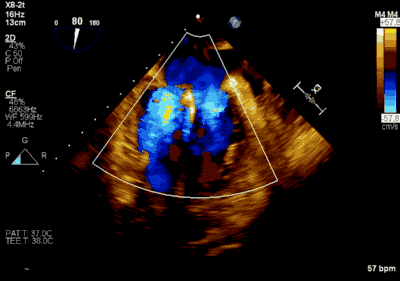

▲ 术后超声检查显示轻度二尖瓣反流